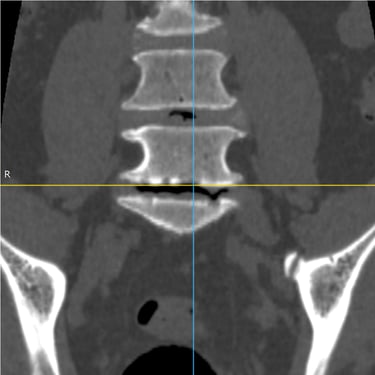

Columna lumbar inestable con listesis: tratamiento con artrodesis y tornillos transpediculares

La listesis lumbar ocurre cuando una vértebra se desplaza hacia adelante o hacia atrás respecto a la vértebra inferior, generando inestabilidad de la columna lumbar. Esta condición puede causar dolor lumbar crónico, compresión nerviosa, ciática, debilidad en las piernas o dificultad para caminar. Cuando el tratamiento conservador no es suficiente, la artrodesis lumbar con tornillos transpediculares es una alternativa quirúrgica eficaz. Este procedimiento permite fijar las vértebras afectadas mediante implantes que estabilizan la columna y favorecen la fusión ósea. Con técnicas modernas y abordajes mínimamente invasivos, se logra aliviar el dolor, mejorar la estabilidad vertebral y recuperar la función del paciente.